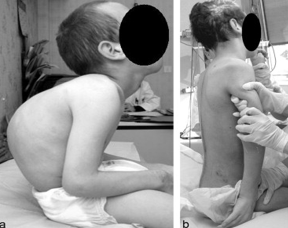

Duchenne Muscular Dystrophy

Inherited progressive myopathic disorder resulting from a defective gene located on the X chromosome that is responsible for the production of dystrophin.

X-linked Recessive

Symptoms:

Muscle Weakness:

Typically occurs at 2 to 3 years of age

Progresses from proximal to distal limb muscles

Affects lower extremities before upper extremities

Children are typically wheelchair-bound by approximately 12 years of age

Decreased endurance; unable to keep up with peers

Toe walking, calf hypertrophy

Muscle cramping

Heart failure and arrhythmias occur late in the disease

Scoliosis—leads to poor pulmonary function

Developmental delays are common

May also present with ADHD, OCD, anxiety, and autism

Diagnosis:

Elevated creatine kinase (CK) levels

Muscle biopsy for definitive diagnosis (shows absence of dystrophin)

**Gower’s Sign (as shown in picture—uses hands to "walk up" the legs when standing from a sitting or lying position)

Treatment:

Administer corticosteroids and calcium/vitamin D supplements

Promote mobility

Assess and maintain cardiopulmonary function

Provide support (chronic, progressive disease)